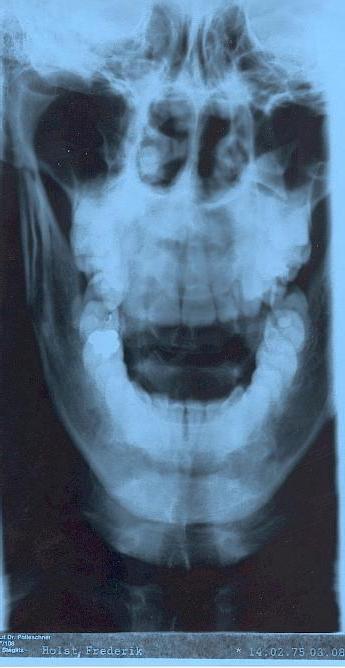

Naja, in ein paar Jahren vielleicht ;-)...

Bis jetzt jedenfalls eher

so

.